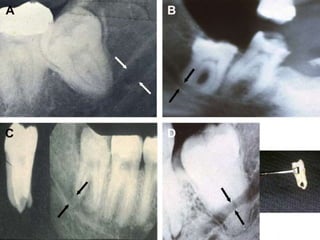

Imaging Studies

• Four conditions can be identified:

(1) superimposition, in which the roots and IAC are

overlaid in the 2-dimensional radiograph but are

actually not in physical contact or proximity;

(2) notching of the root, in which the IAC is in intimate

physical contact within an indentation in the side of the

root;

(3) grooving, in which the IAC is in intimate contact

within a concave defect in the apex of the root;

and (4) perforation, in which the IAC actually

penetrates through the root .

• Conditions other than superimposition might

require further evaluation with a computed

tomographic scan .

Radiologic criteria indicating need for

CT scan

ADJ 2011(Kim ,et al.)